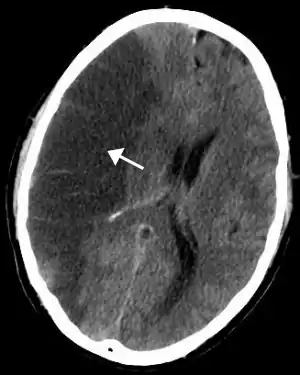

Intracerebral hemorrhage

It generally occurs in small arteries or arterioles and is commonly due to hypertension,[49] intracranial vascular malformations (including cavernous angiomas or arteriovenous malformations), cerebral amyloid angiopathy, or infarcts into which secondary hemorrhage has occurred.[2] Other potential causes are trauma, bleeding disorders, amyloid angiopathy, illicit drug use (e.g., amphetamines or cocaine). The hematoma enlarges until pressure from surrounding tissue limits its growth, or until it decompresses by emptying into the ventricular system, CSF or the pial surface. A third of intracerebral bleed is into the brain's ventricles. ICH has a mortality rate of 44 percent after 30 days, higher than ischemic stroke or subarachnoid hemorrhage (which technically may also be classified as a type of stroke[2]).